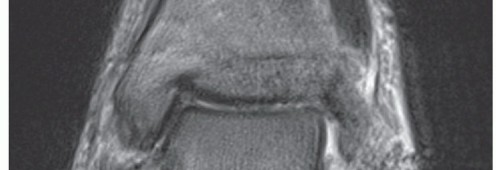

A computed tomography (CT) scan may be obtained to detect a talocalcaneal coalition or bony fragmentation that involves the articular surfaces. A weight-bearing CT may be beneficial to recognize the specific position of talus within the ankle mortise and a potential incongruency in the subtalar joint, as given by an accompanying peritalar instability (FIG 3).

55 FIG 3 • Weight-bearing CT in a patient with severe instability (same patient in FIG 2C). A. AP coronal plane.

B. Sagittal plane. C. AP horizontal plane.*